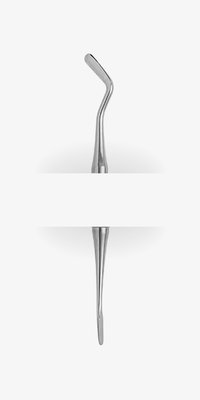

| Značka | MEDESY |

| Dodavatel | Medident Sk |

| SKU | MED 860 |

| Kategorie | Ordinace > Ruční nástroje > Nástroje chirurgické > Raspatoria |